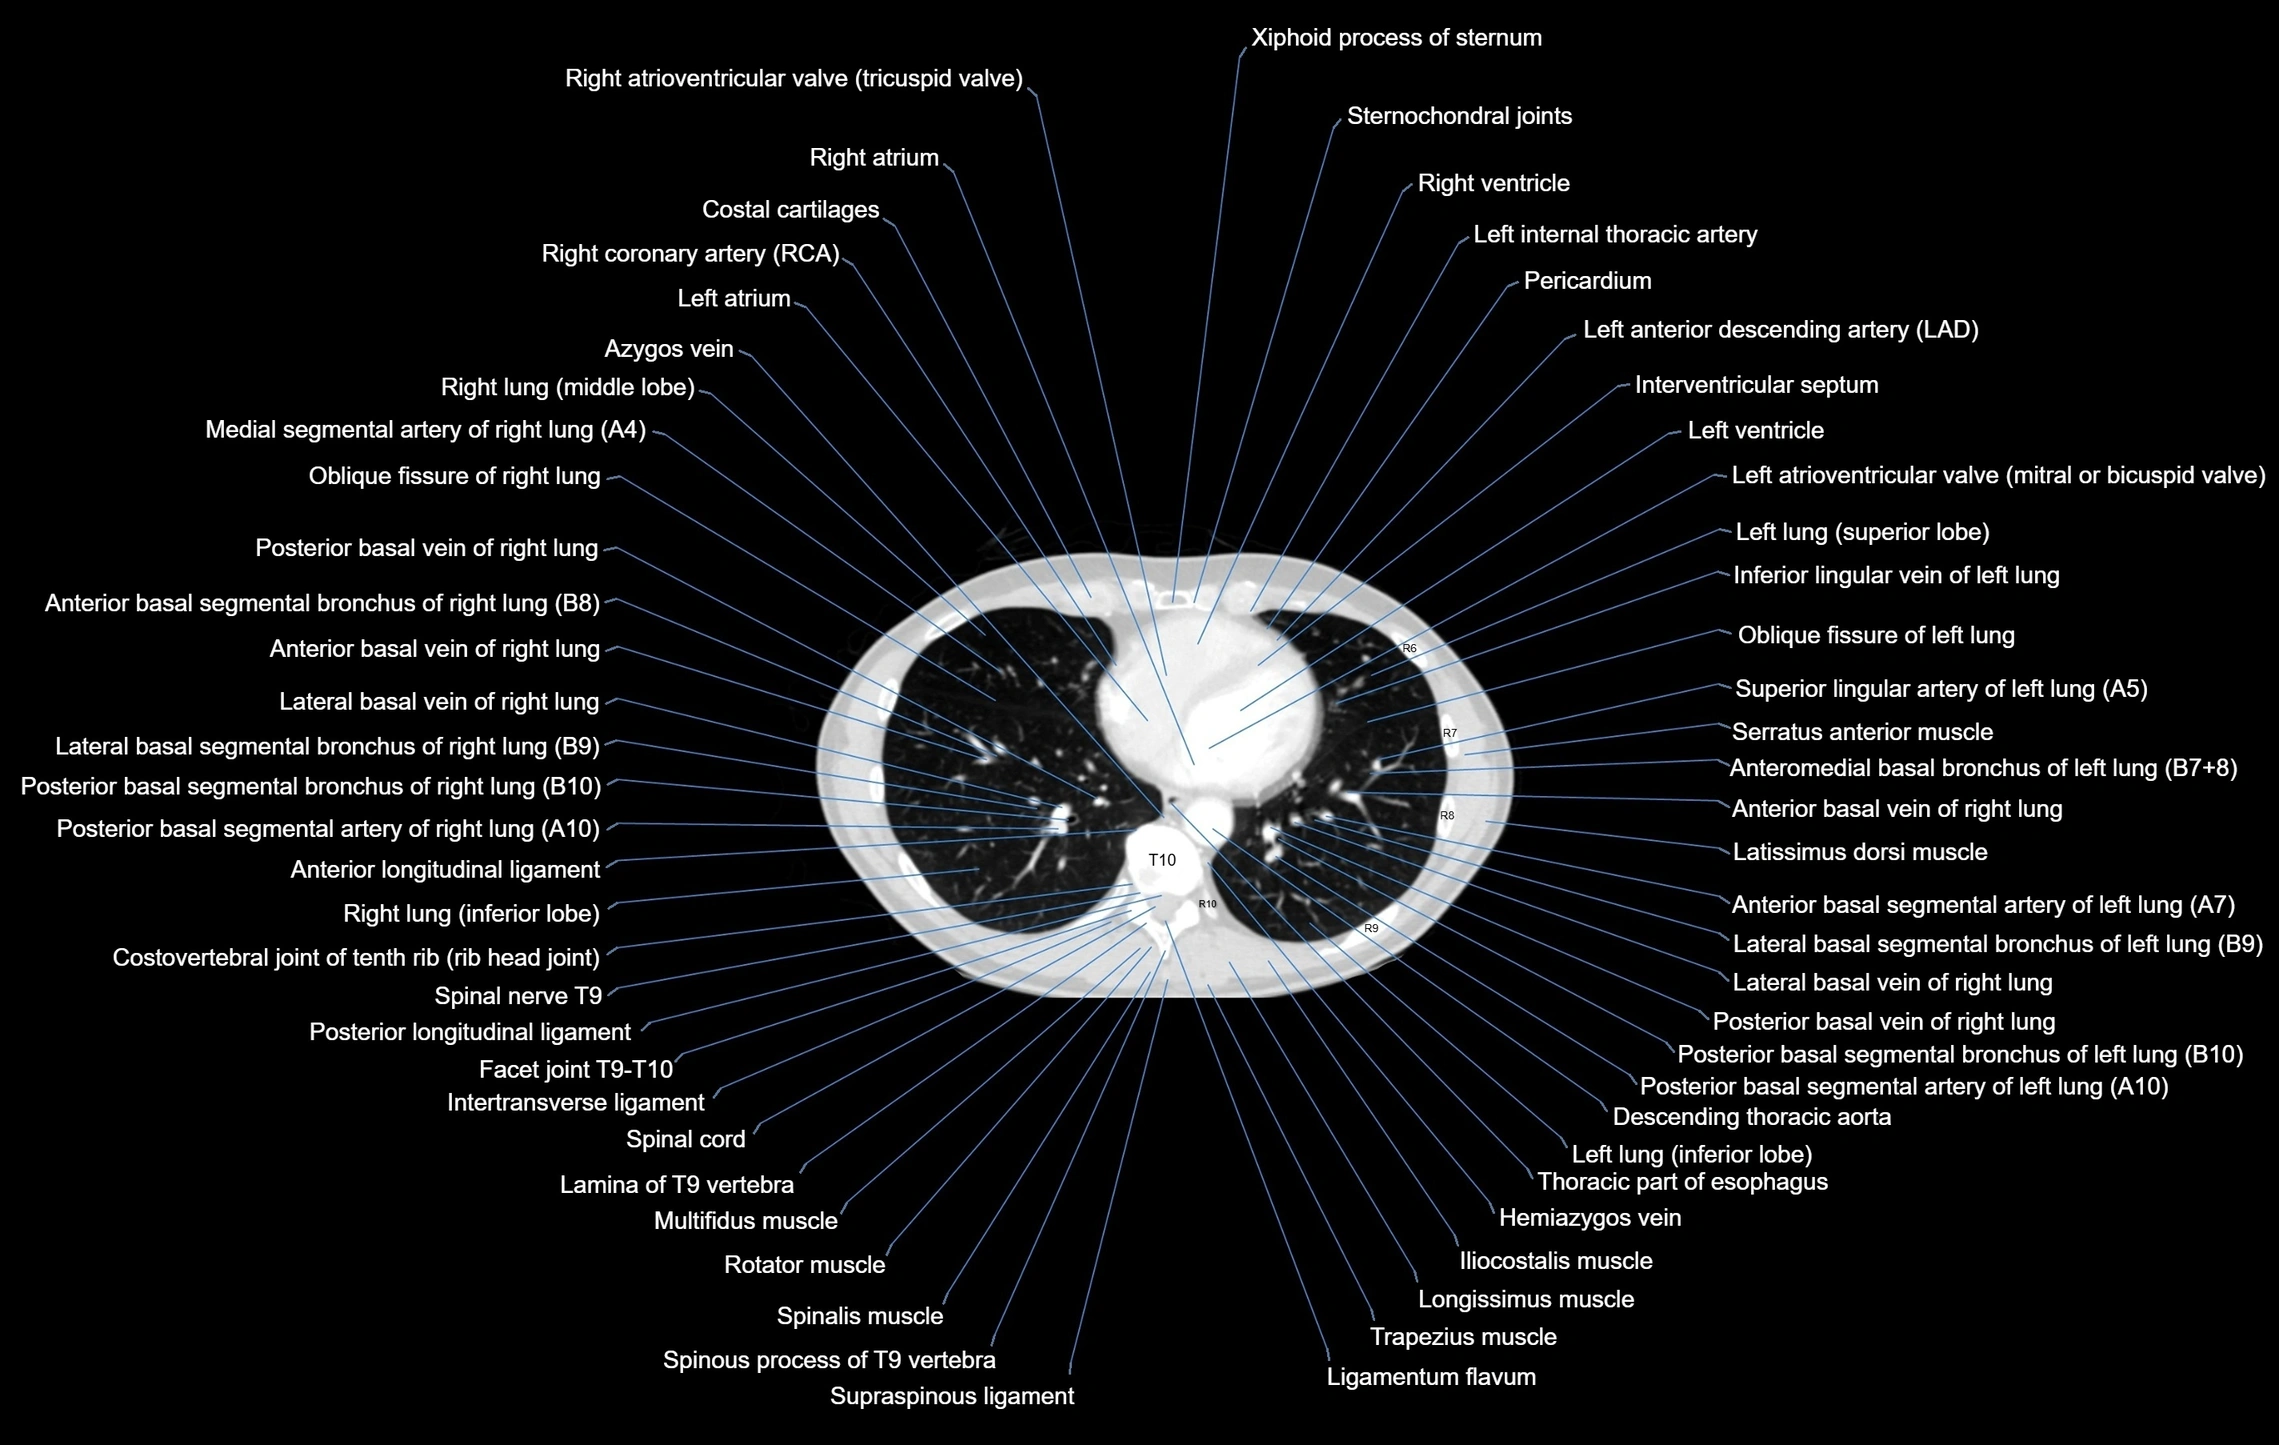

- Right atrioventricular valve (tricuspid valve)

- Right atrium

- Costal cartilages

- Right coronary artery (RCA)

- Left atrium

- Azygos vein

- Right lung (middle lobe)

- Medial segmental artery of right lung

- Oblique fissure of right lung

- Anterior basal segmental bronchus of right lung (B7+8, B8)

- Posterior basal vein of right lung

- Lateral basal segmental bronchus of right lung (B9)

- Posterior basal segmental bronchus of right lung (B10)

- Posterior basal segmental artery of right lung

- Anterior basal segmental artery of right lung

- Anterior longitudinal ligament

- Inferior lobe of right lung

- Costovertebral joint

- Spinal nerves

- Posterior longitudinal ligament

- Facet joint of vertebra (Zygapophyseal joints)

- Intertransverse ligament

- Multifidus muscles

- Rotatores muscle

- Descending thoracic aorta

- Thoracic part of esophagus

- Hemiazygos vein

- Latissimus dorsi muscle

- Trapezius muscle